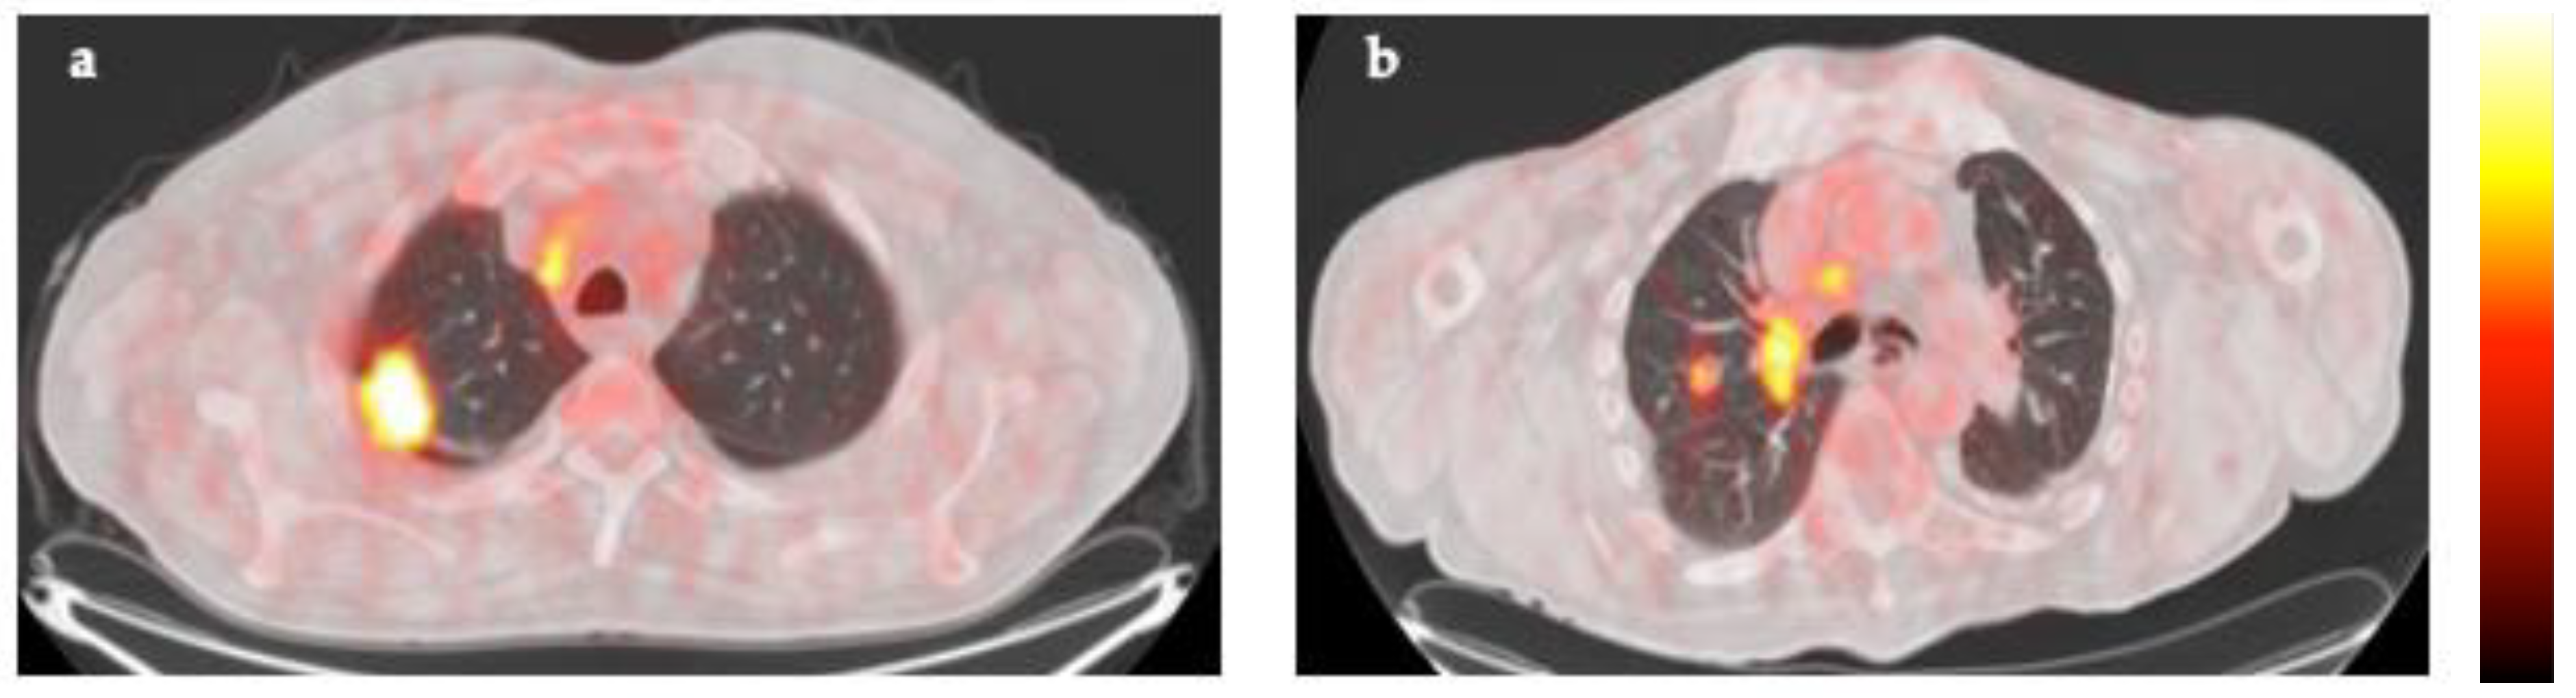

18F-FDG PET/CT scans were analyzed and imaging parameters were extracted from metastatic lymph nodes and primary tumors. Figure 1 shows representative images of the VOIs drawn around the targeted lymph node and primary tumor in a patient with stage IIIA NSCLC.

Figure 1. Representative images of 18F-FDG PET/CT scan in a patient with stage IIIA non-small cell lung cancer. (a). Maximal intensity projection PET image; (b). transaxial fusion image of co-registered PET and CT showing high FDG uptake in the primary lung tumor and hilar lymph node. A tridimensional region of interest was drawn around the primary lung tumor (green); (c). corresponding CT image of the thorax using window for lung parenchyma visualization; (d). transaxial fusion image of co-registered PET and CT showing the FDG avid metastatic hilar lymph node. A tridimensional region of interest was drawn around the targeted lymph node (pink); (e). corresponding CT image of the thorax using window for mediastinal visualization.